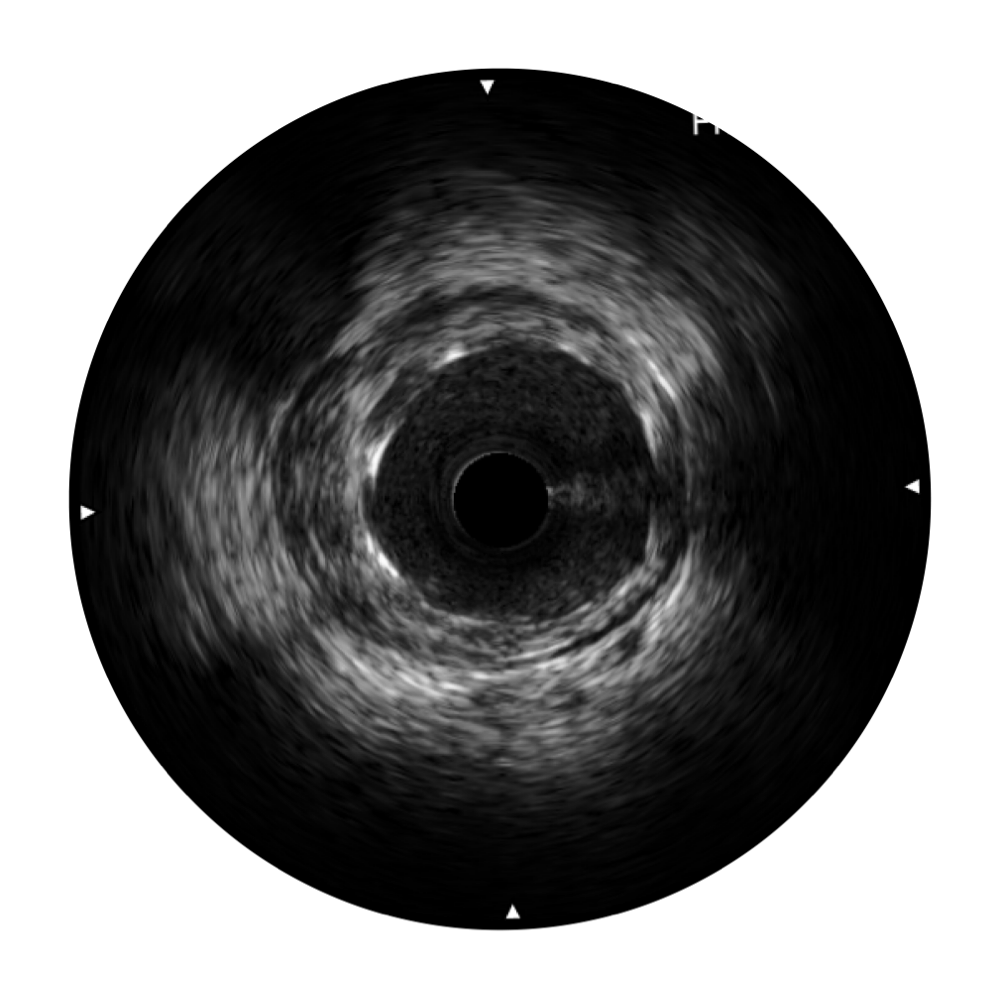

• 美狮贵宾会官网宽频IVUS图像

对比传统IVUS导管成像,美狮贵宾会官网宽频IVUS图像的近场支架梁显影更细腻,远场中膜外血管仍清晰可辨,兼顾远中近,兼顾分辨力与穿透深度